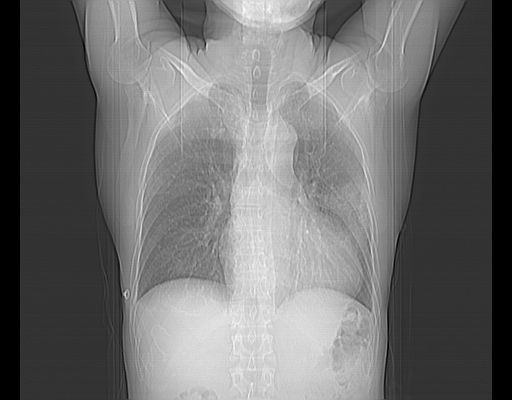

标题: CT25795:感冒后反复咳嗽两月余,痰中带血半月余。X诊断“肺 [打印本页]

标题: CT25795:感冒后反复咳嗽两月余,痰中带血半月余。X诊断“肺

1.双肺肺梗塞(理由:病灶呈三角形,与胸膜相连且局部胸膜肥厚,左心室增大)伴肺感染。

考虑两肺感染性病变,左肺上叶舌段肿瘤性病变待排;建议抗炎治疗后复查。